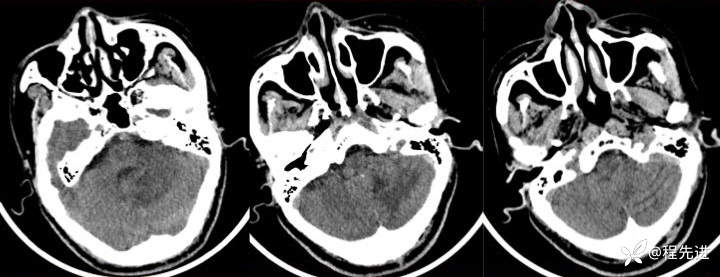

T2:

img